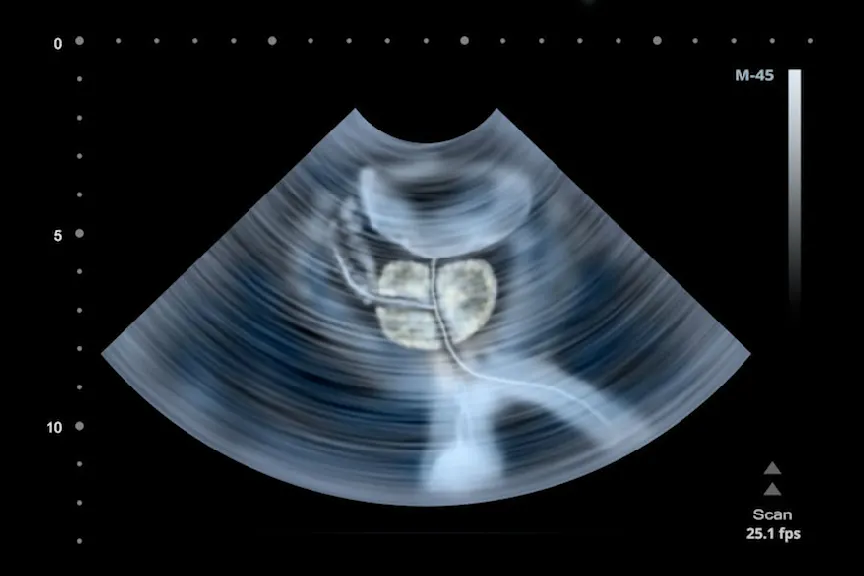

什么是前列腺癌?

癌症的前列腺癌是一个严重的健康问题后皮肤癌它是美国男性中第二大最常见的癌症,仅次于肺癌是癌症致死的原因每年,被诊断出患有前列腺癌的男性是死于前列腺癌的男性的8倍。